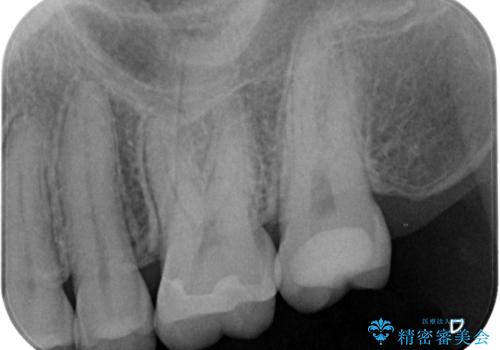

- 数年前他院にて治療した銀歯をやり替え希望の患者様です。

拡大鏡下で、銀歯、むし歯の除去を行い、セラミックインレーに適した形に整えました。